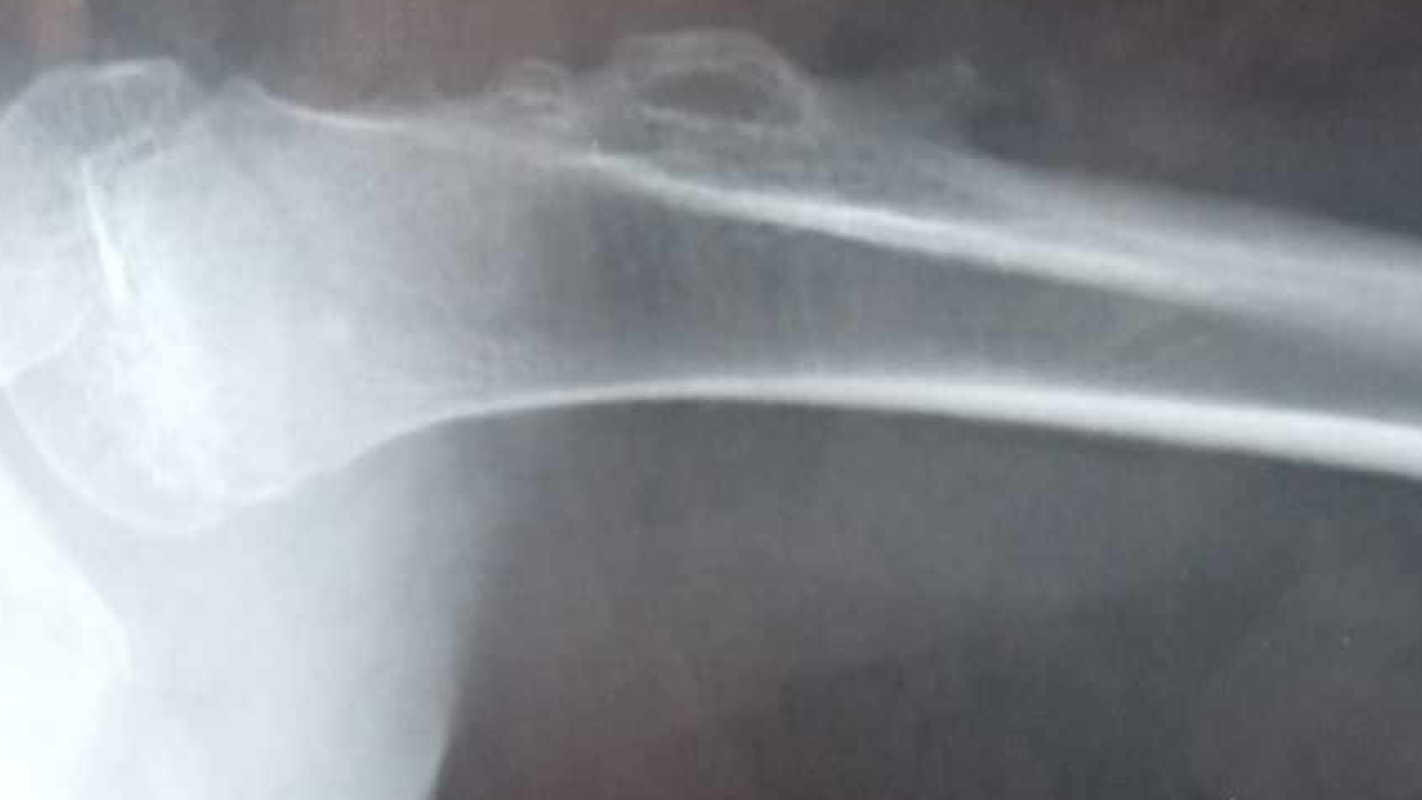

I would like to raise money for my daughter's medical condition. She has osteochondra which is cancerous. We have a biopsy coming up. We have to travel down state once a month. We have to find rides because our vechile is not safe enough and keeps shutting off while we are driving. We have another appointment coming up February 29th and then we will have one March 17/18 for her to get her pain under control